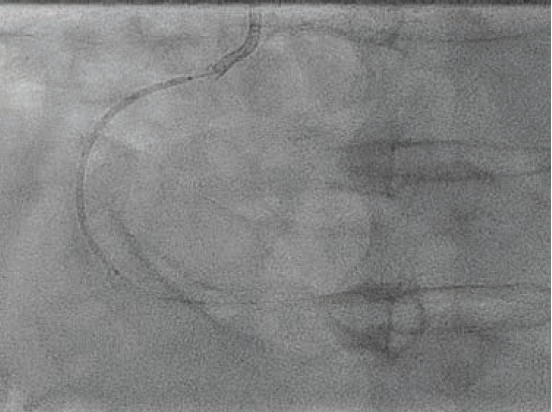

Based on the distal reference diameter of 3.6 mm (Figure 3), we tried to perform one more round of pre-dilation with a 3.5 mm Emerge™ Monorail PTCA dilatation catheter (Boston Scientific). This did not cross, and resulted in kinking of the LiquID® guide catheter extension. Both were removed, and a 6 French GuideLiner™ Coast™ Catheter (Teleflex) was inchwormed into the mid vessel utilizing the used 3.0

mm NC Takeru™ PTCA balloon dilation catheter as an anchor. More aggressive pre-dilation was performed with the 3.0 mm NC Takeru™ in the mid segment. Then, a 3.5 mm x 48 mm Synergy™ XD DES was successfully positioned in the mid-distal vessel (Figure 4) and deployed at nominal pressure.